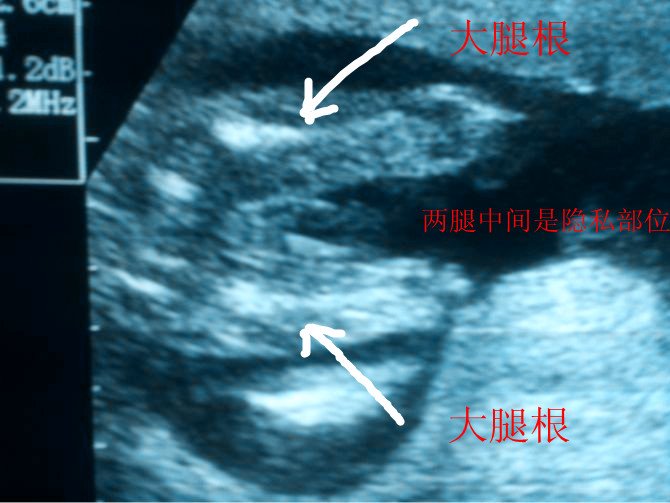

找熟人做的B超拍下的宝宝隐私部位图看不懂是男孩女孩 内行的人帮看看 患者信息:女 25岁 广西 河池 病情描述(发病时间、主要症状等):找熟人做的B超看不懂是男孩女孩 内行的人帮看看 我没有积分送大家希望好心人帮看看 谢谢想得到怎样的帮助:找熟人做的B超看不懂是男孩女孩 内行的人帮看看曾经治疗情况及是否有过敏、遗传病史:没有好心人帮看看谢谢 点击展开 匿名用户 2012-09-20 23:18 满意回答 男孩,可以肯定,女孩在B超里显示的没有条状物的 匿名用户 2012-09-21 14:59 宝宝知道提示您:回答为网友贡献,仅供参考。 为您推荐: 其他回答 模糊 匿名用户 2012-10-05 14:05 应该是男孩 匿名用户 2012-09-25 21:44 看不清 凭睿博_dPjV 2012-09-20 23:30 男孩 匿名用户 2012-09-20 23:27 相关问题 这是今天做的b超单,有内行的医生可以帮我看看胎儿正常吗?现在能看出是男孩女孩吗? 哪位内行的宝妈帮我看看我这个结果是男孩女孩呢?10月6号B超显示双顶径:7 0cm股骨长:5 6c 男孩女孩住一个房间 但都比较隐私怎么装修

患者信息:女 25岁 广西 河池 病情描述(发病时间、主要症状等):找熟人做的B超看不懂是男孩女孩 内行的人帮看看 我没有积分送大家希望好心人帮看看 谢谢想得到怎样的帮助:找熟人做的B超看不懂是男孩女孩 内行的人帮看看曾经治疗情况及是否有过敏、遗传病史:没有好心人帮看看谢谢